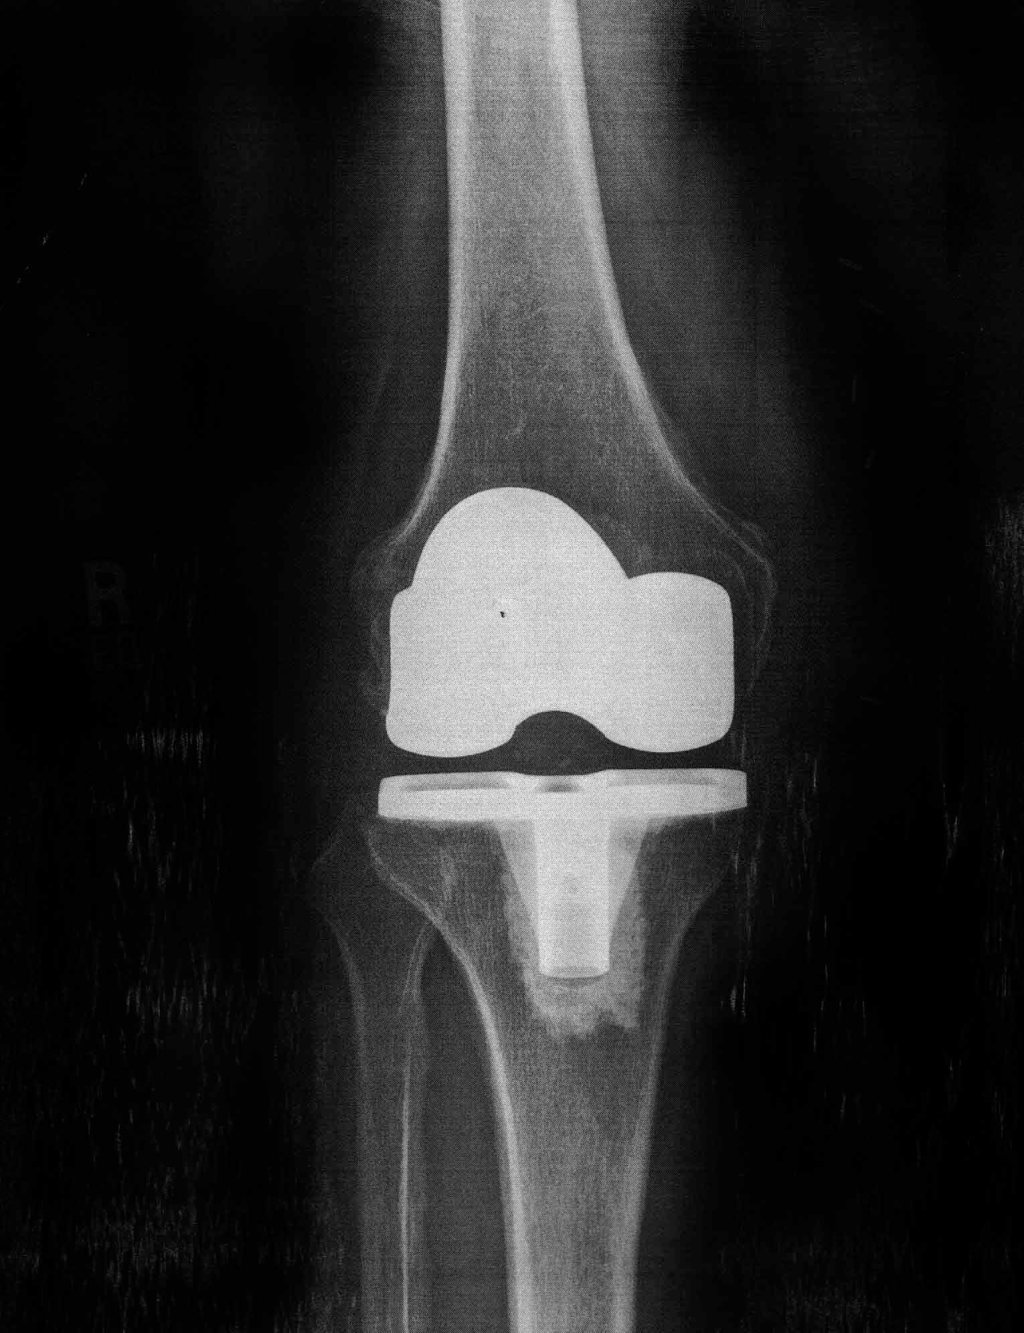

There it is, my new knee.

Yesterday I had my 6-week checkup; they were kind enough to print out the x-ray for me. Gail won’t let me post it on the refrigerator, so I’m putting it up here.

You can see the new metal parts. The open space between them is a plastic spacer (invisible to x-rays) that should last a lifetime–and they can replace it with relatively minor surgery if I have too much fun and wear it out.